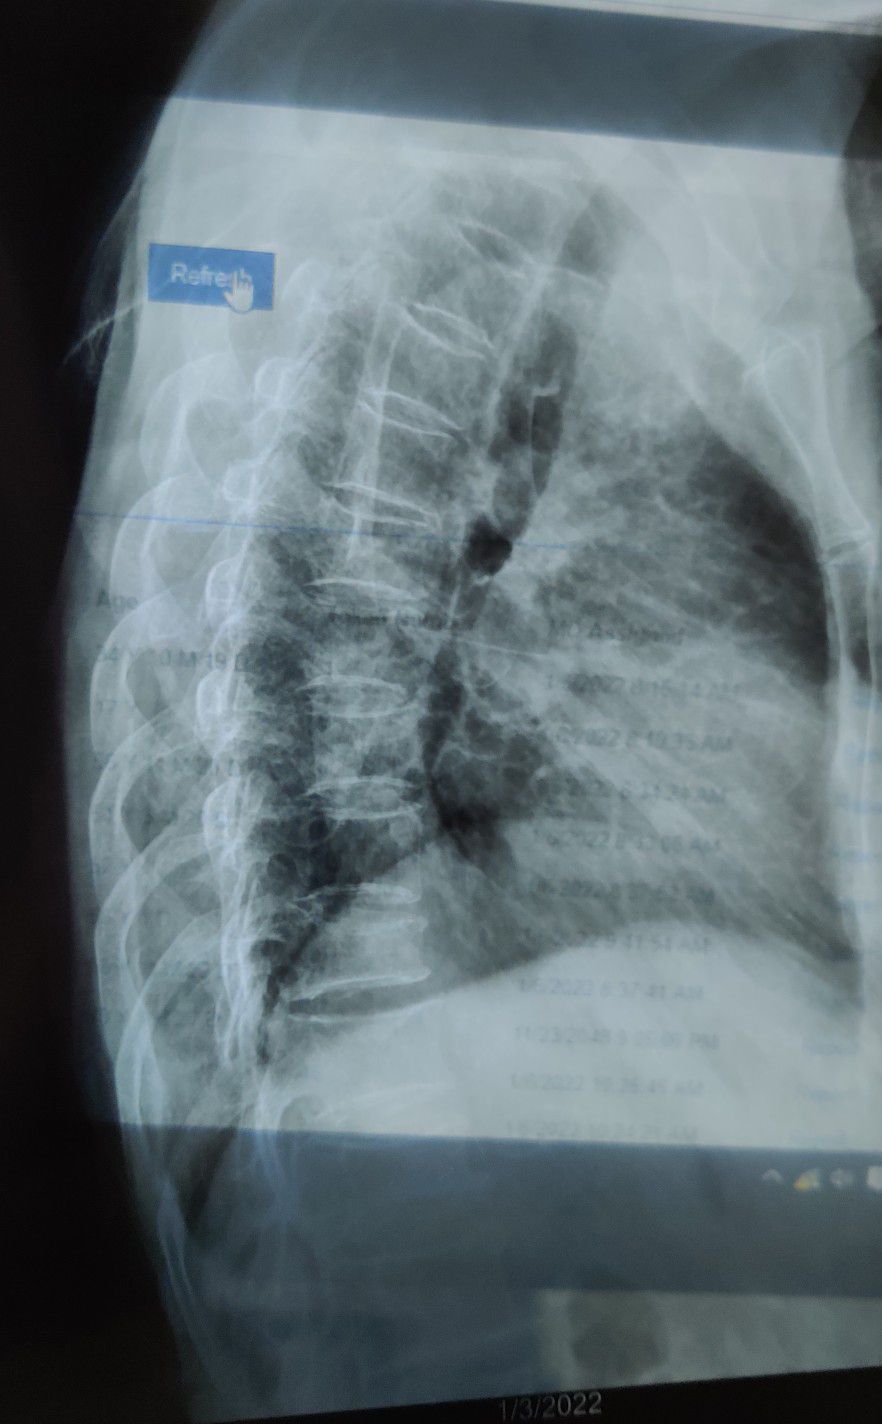

Kyphosis with osteoporosis

Spine

Ortho

Kyphosis